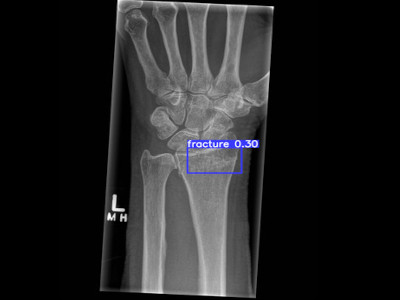

Detecção de fratura do rádio distal em Raio X

Fratura do rádio distal